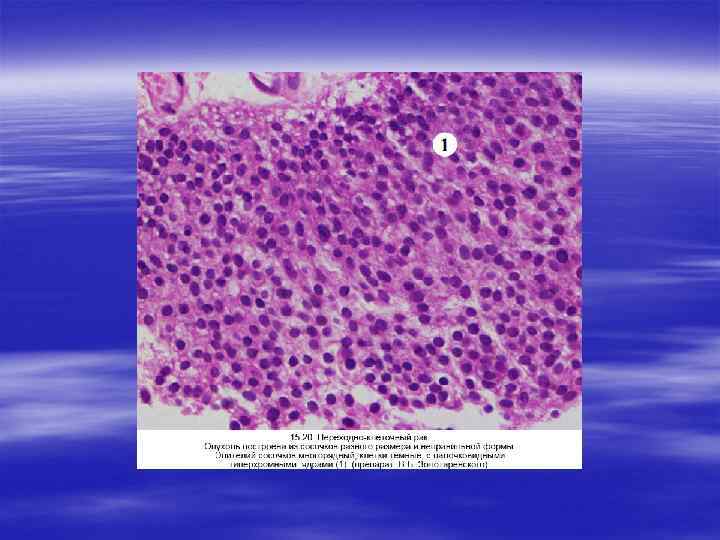

ОПУХОЛИ § В мочевыводящей системе встречаются различные опухоли, как доброкачественные, так и злокачественные. Из доброкачественных чаще развиваются аденомы и фибромы коркового слоя почек, из злокачественных — гипернефроидный рак, опухоль Вильмса, кар цинома почечной лоханки, мочеточников и мочевого пузыря.

ГИПЕРНЕФРОИДНЫЙ РАК ПОЧЕК § Гипернефроидный (светлоклеточный) рак почек относится к наиболее часто встречающимся злокачественным опухолям (в 80— 90 % случаев). У мужчин наблюдается в два раза чаще, чем у женщин, преимущественно в возрасте 50— 70 лет. Источник развития карциномы — клетки канальцевого эпителия. По своему строению опухолевые клетки весьма сходны с клетками коры надпочечников, в связи с чем этот вид опухоли получил название гипернефроидного